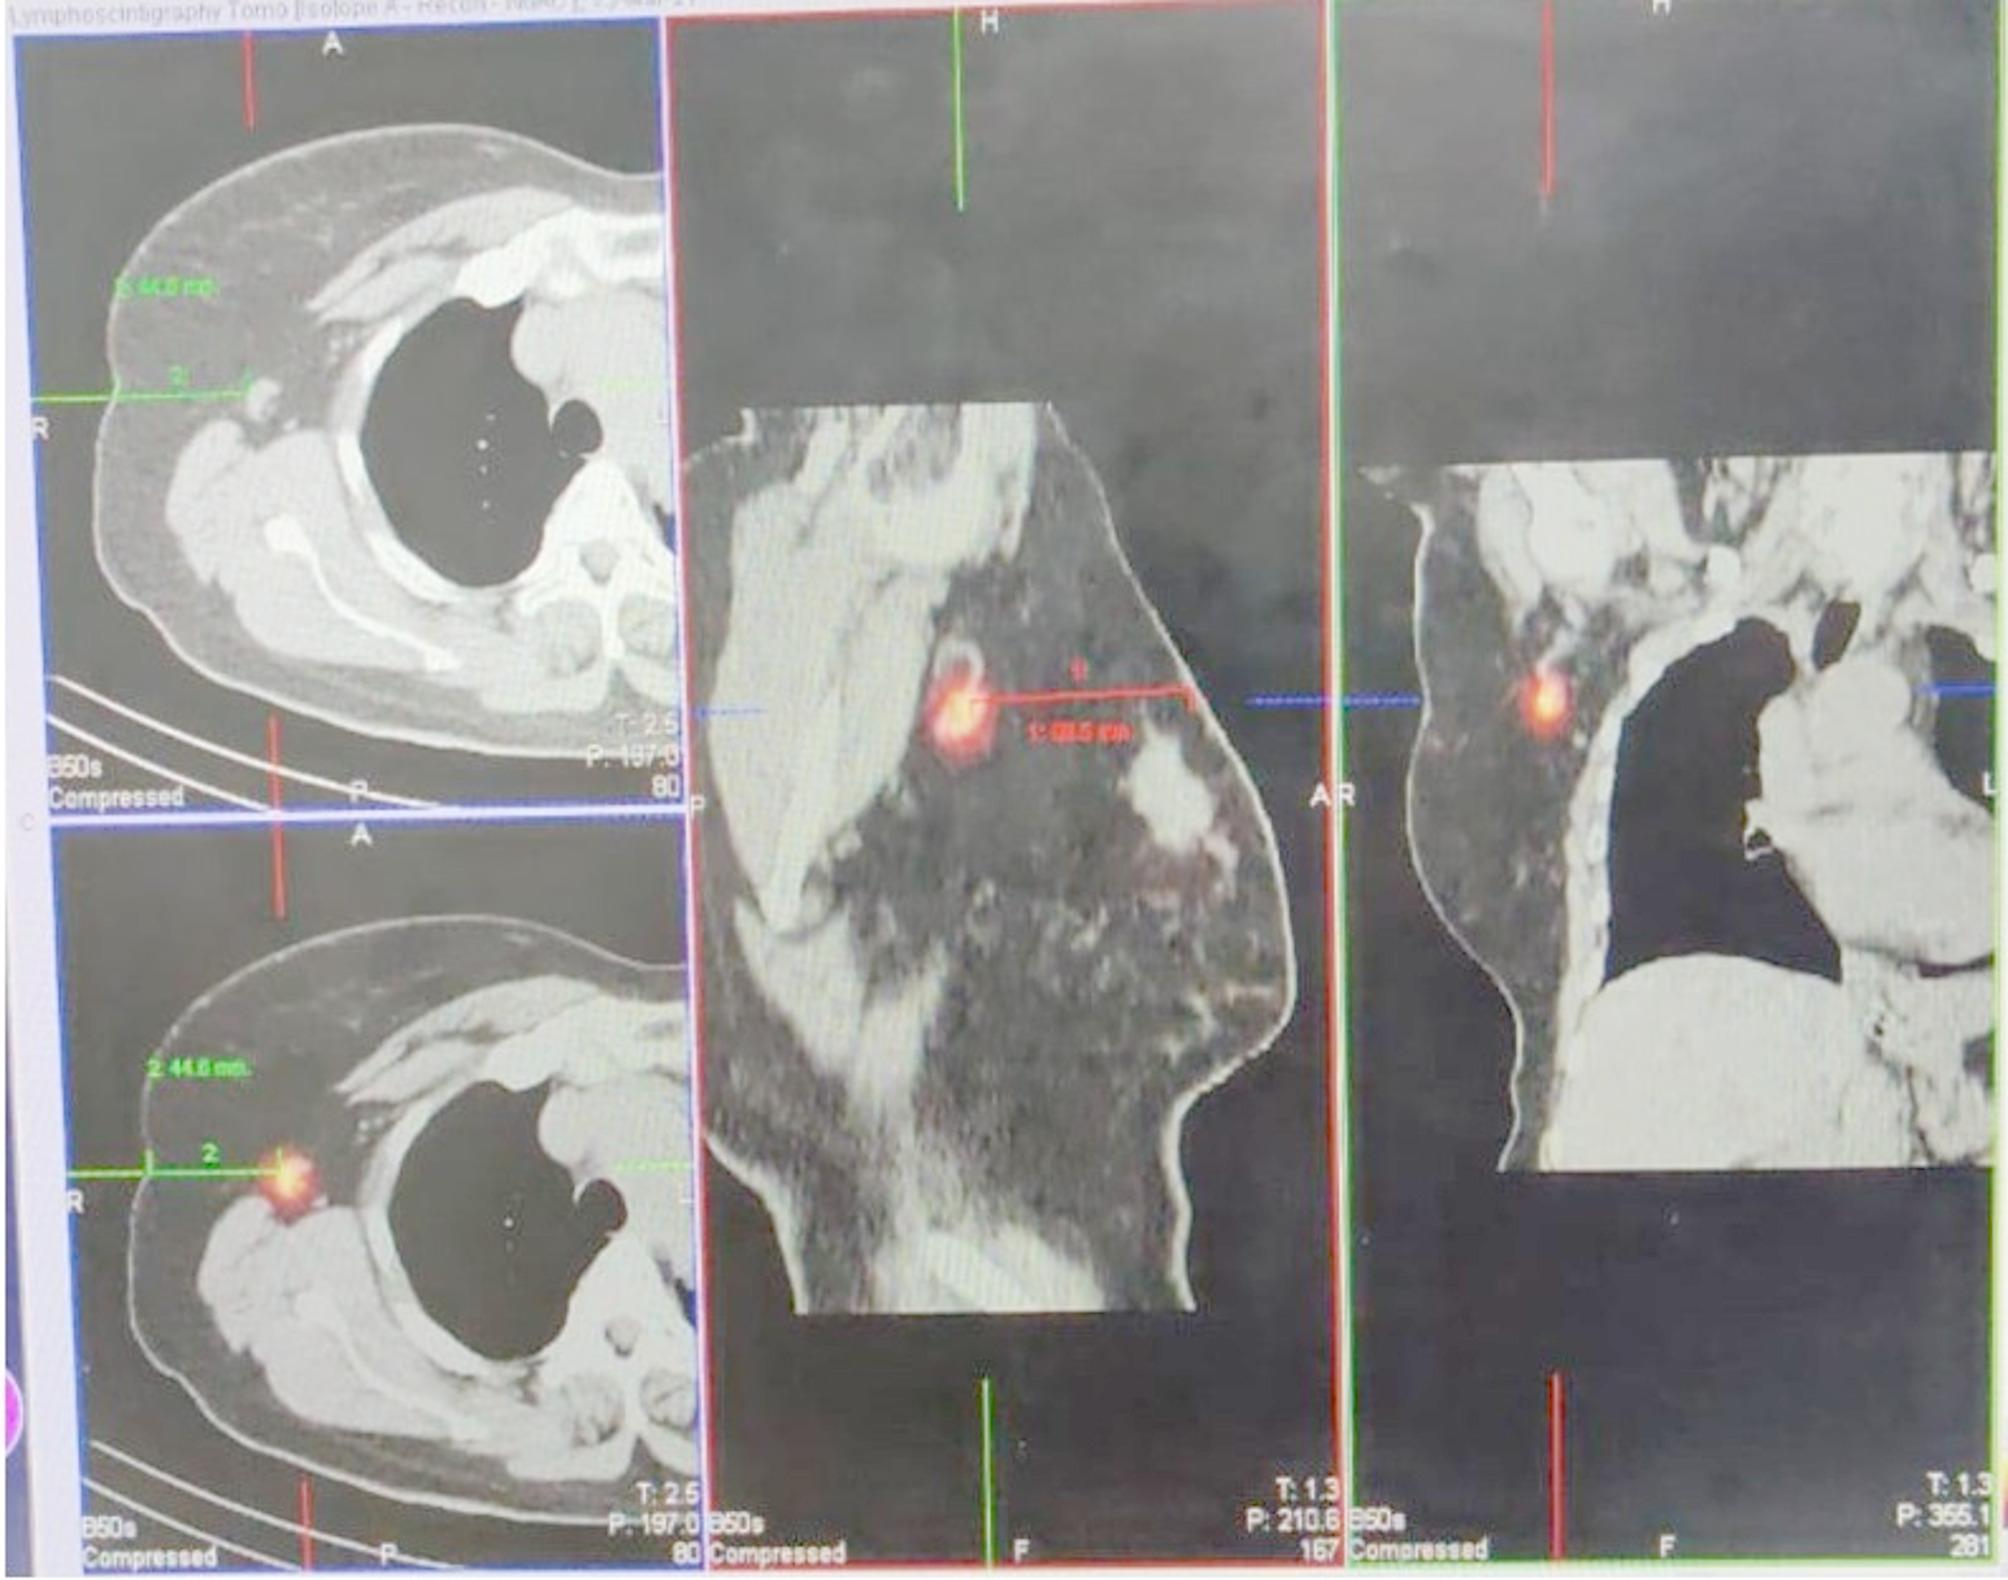

Aim: To demonstrate the safety and feasibility of sentinel node biopsy using methylene blue and SPECT CT lymphoscintigraphy.

Results: Out of a total of 628 patients operated for the above cancers, 70 patients underwent a sentinel lymph node biopsy along with surgery for the primary. Localization was possible in all the patients (100%). The time taken to localize the node decreased from 33 min to 16 min over the course of the learning curve (percentage change of -50%). The median number of nodes isolated increased by 200% and the seroma in the nodal basin decreased by 26%. Recurrences in the nodal basin were commonest in penile cancer (16.6%), while those in the axilla (6.5%) could be salvaged surgically.